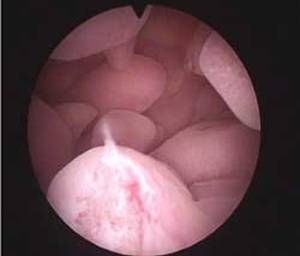

图一 宫腔镜检查:正常宫腔

图二 宫腔镜检查:发现子宫内膜多发息肉